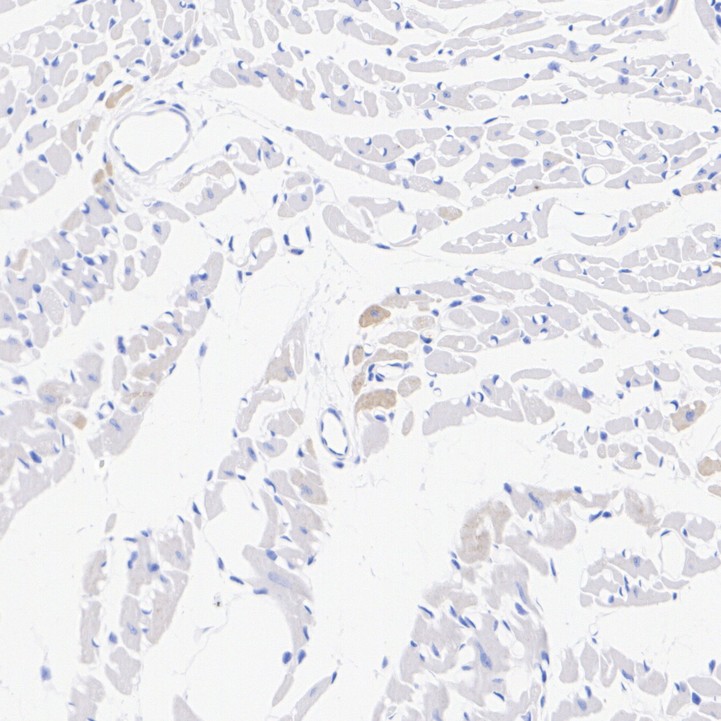

Slow Skeletal Myosin Heavy chain Recombinant Rabbit Monoclonal Antibody [PSH07-54] - BSA and Azide free

Catalog# HA751092

IHC-P